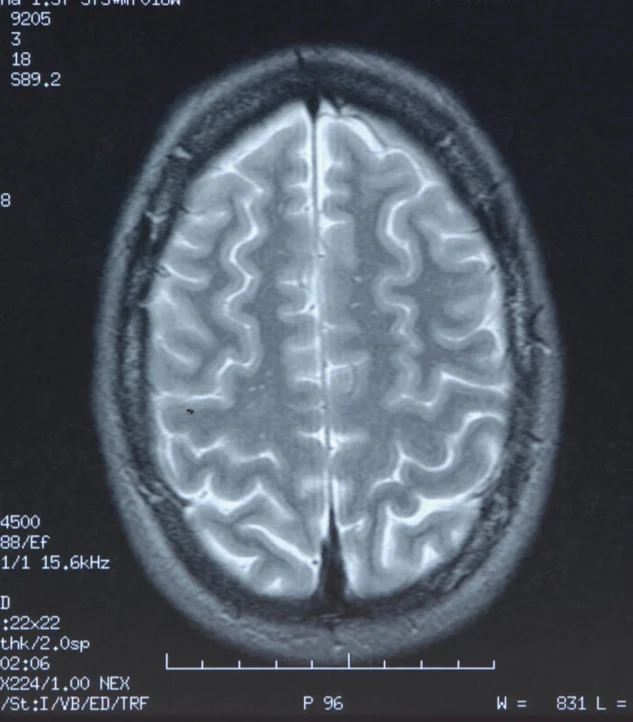

Praise was profoundly depressed at birth and required extensive resuscitation. He survived, but with severe neurological brain injuries which rendered him blind, with quadriplegic cerebral palsy, unable to communicate, and fully dependent for all activities of daily living. Praise lived in that condition until 2020, when he died from his neurological injuries.